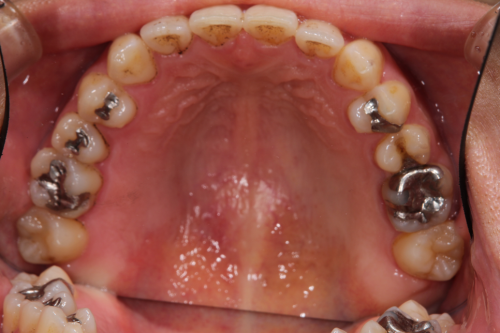

銀歯を白い詰め物に変えました。

左上は虫歯が大きかったのでゴールドインレーで対応してます。見た目はあまり良くありませんが、ゴールドが一番歴史があり信頼できる方法とも言えます。

ゴールドインレー

費用11万円

リスクとして見た目がよくない、汚れがつきやすいことがあげられる。